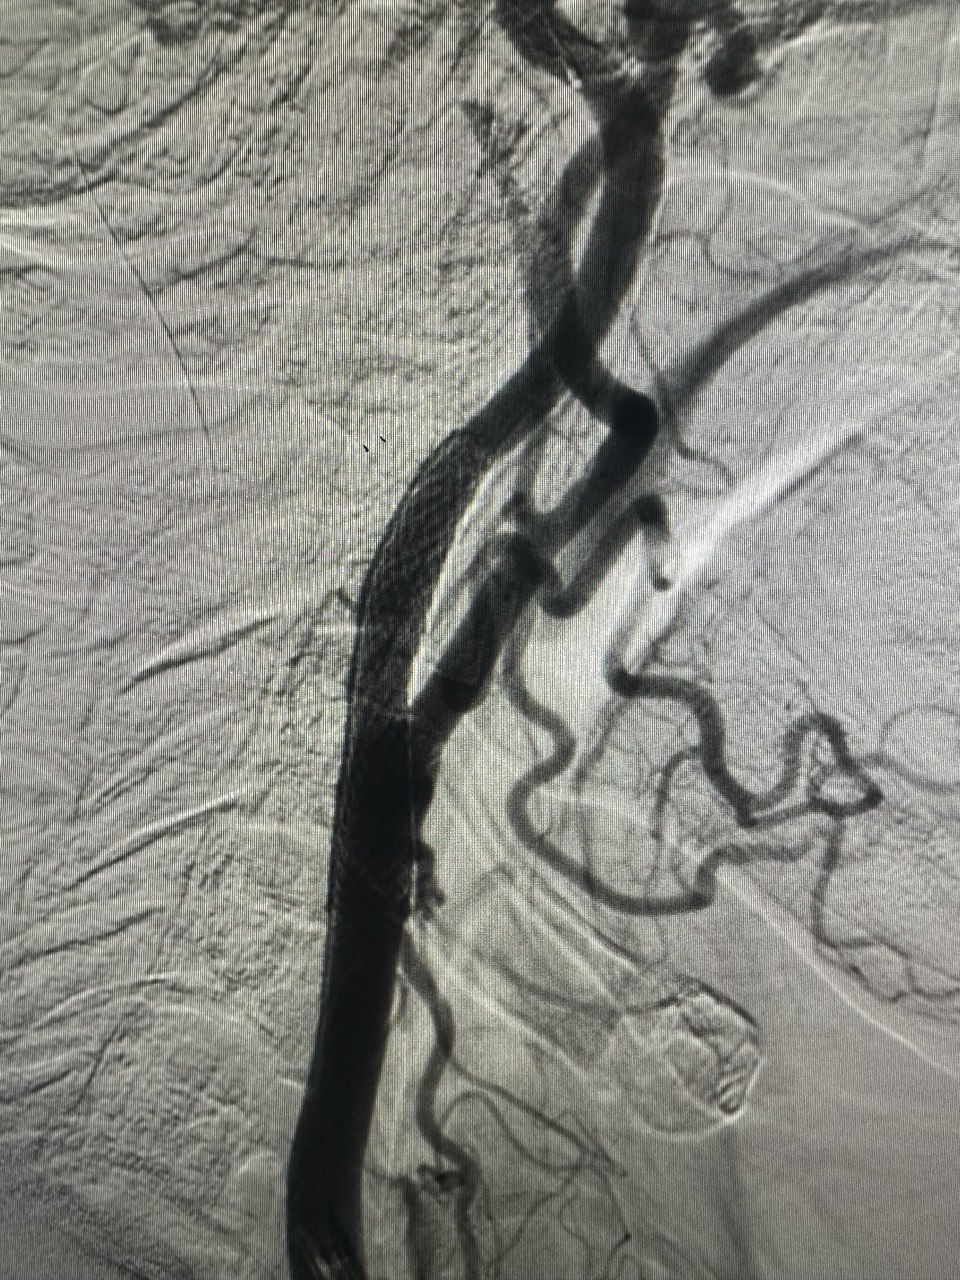

Стентування сонних артерій (CAS) – це процедура, яка виконується для відкриття звуженої сонної артерії. Вона полягає і розміщенні стенту (сітчаста трубка) в звужену артерію. Ця процедура також називається каротидною ангіопластикою.

Є дві сонні артерії (по одній з кожного боку шиї), які кровопостачають мозок. Ці артерії можуть бути звужені та пошкоджені жировими відкладеннями (атеросклеротичними бляшками). Ця бляшка може обмежити приплив крові до мозку, що підвищує ризик інсульту.

Стеноз сонної артерії до та після стентування

Під час стентування сонної артерії в сонну артерію вставляється стент (невелика сітчаста трубка, що розширює артерію зсередини).

Для введення стенту лікар використовує іншу трубку, яка називається катетером. Лікар вводить катетер у кровоносну судину в паху чи зап’ясті і переміщає його до сонної артерії.

Усередині катетера знаходиться дуже тонкий провідник. Провідник використовується для переміщення балона та стента в сонну артерію. Балон поміщають усередину стенту і надувають. Це відкриває стент та притискає його до стінок артерії. Потім балон здувають та видаляють, залишаючи стент на місці.